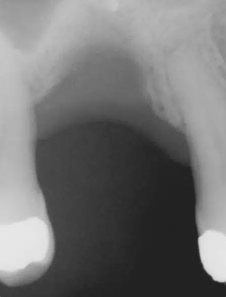

Presentamos el caso de un paciente masculino de 69 años, en el que se realizó la extracción dental seguida de la colocación de un implante Bicon SHORT® de 6,0 x 5,0 mm con pilar de elevación de seno.

El caso se restauró con una corona de pilar integrado (IAC) de 20 mm de longitud y ha sido seguido durante 84 meses.

Este caso destaca no solo por la estabilidad a largo plazo del implante corto, sino también por mostrar de forma radiográfica la aplicación de la Ley de Wolff: el hueso se adapta y se refuerza en respuesta a la carga funcional.